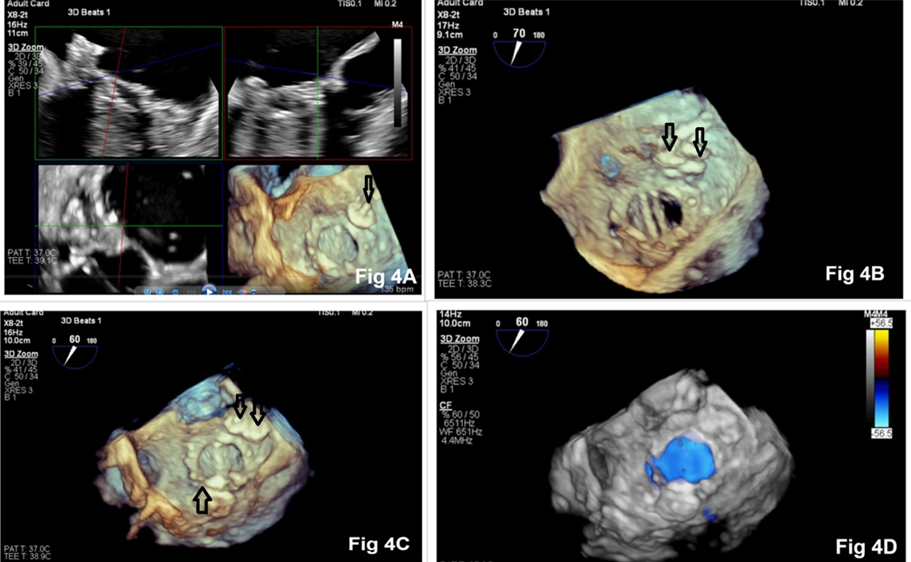

transcatheter closure of the PVLs to the patient and, informed consent was obtained. Considering the complexity and duration of the procedure, along with the requirement of intraoperative TEE, the procedure was performed under general anaesthesia in a hybrid operating room. En-face view of the mitral valve showed severe PVLs through 3 defects: two at the 2 o’clock position and one at the 7 o’clock position (Figure 2A, 2B). Antegrade trans-septal approach via the femoral vein was chosen for PVL closure (Fig 3A). A telescoping coaxial system was introduced into the LA, including a trans-septal LA sheath. An 8.5 F Agilis NXT Steerable introducer, a 6 F coronary guide (multipurpose catheter), and a 5 Fr multipurpose diagnostic catheter were used during the procedure (Figure 3B). Fluoroscopy with RT-3D TEE was used for the successful insertion of the guide wire through the defects. All three PVLs were closed successfully with AmplatzerTM Vascular Plug II devices in a stepwise manner (Figure 4A, 4B, 4C). At the end of the procedure, there was no residual PVL (Fig 4D). The patient made an uneventful recovery.

Figure 4: 3D en face view of the mitral valve showing placement of the first, second, and third Amplatzer™ vascular plug devices (Fig 4A, 4B, 4C). There was no paravalvular leak at the end of the procedure (Fig 4D).